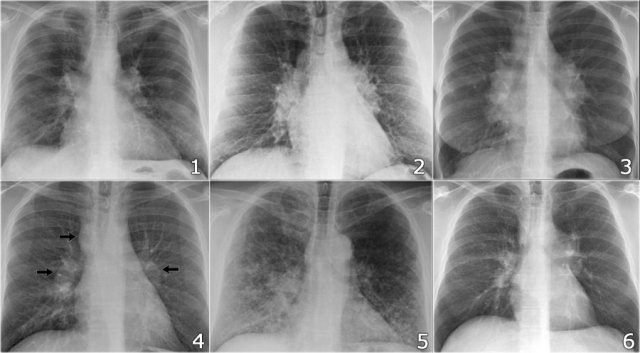

Case Example: Subtle Signs of Congestive Heart Failure

Begin by reviewing these current chest radiographs.

Based solely on these images, one might suspect congestive heart failure (CHF), though the findings are subtle.

Now review the previous study…

Scrolling between the current and prior films significantly increases diagnostic confidence in your diagnosis of congestive heart failure.

Key comparative findings include:

• Cardiac size: Slightly increased compared to the previous study; however, cardiomegaly was already present.

• Pulmonary vasculature: Mild vascular engorgement suggesting elevated pulmonary venous pressure.

• Interstitial markings: Subtle signs of interstitial edema .

• Pleural effusions: Bilateral small effusions, with subtle changes in the inferoposterior borders of the lower lobes, suggesting fluid accumulation.